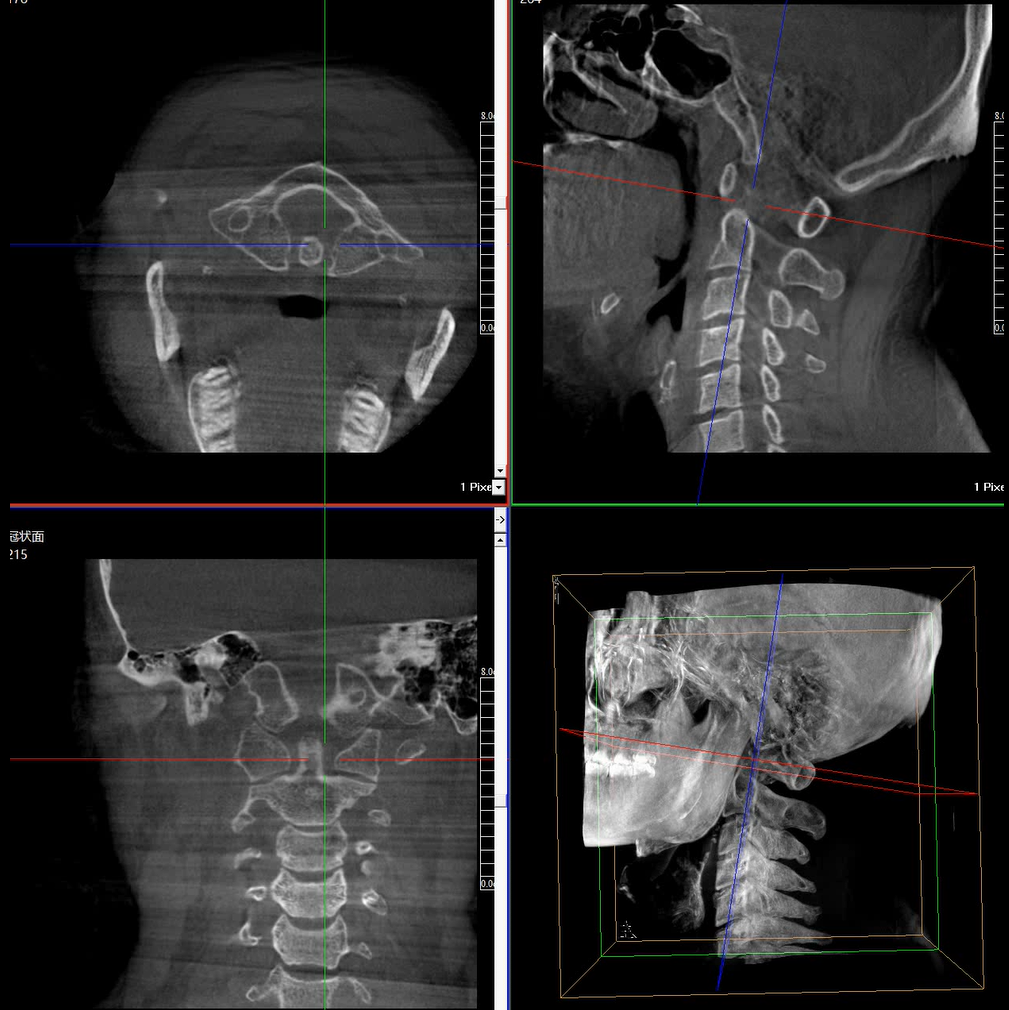

提供更大的術(shù)中三維成像視野,采集更多圖像信息,可一次拍全全段頸椎、全段腰椎、七節(jié)胸椎、雙側(cè)骶髂關(guān)節(jié)、股骨頭及單側(cè)盆骨。

在C臂掃描過程中,始終保持拍攝主體處于射線束的中心,避免了序列圖像采集過程中的橫縱方向運動,減少相對運動造成的運動偽影。